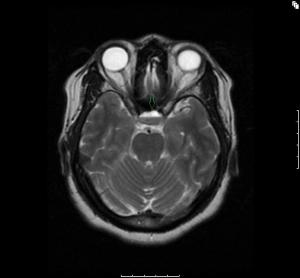

The coexistence of focal seizures and secondary generalized seizures in this patient and the respective EEG and MRI findings constitute her peculiar epilepsy syndrome.